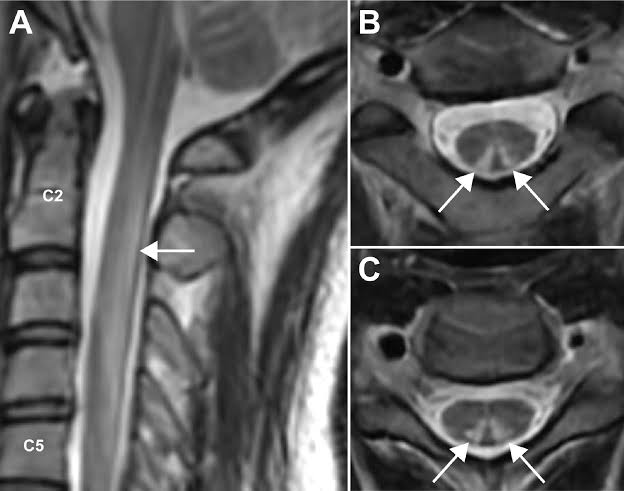

A woman was diagnosed with MS in 2019. A cerebrospinal fluid sample (obtained from spinal anaesthesia in a research study) 15 years prior showed antibodies against Epstein-Barr virus (EBV). A case report from Spain pubmed.ncbi.nlm.nih.gov/41841779/